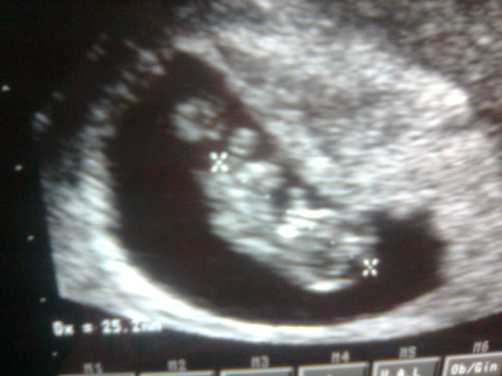

Azonban hoztam nektek meglepi képet tegnapról (9+2)

CRL = 25 mm

ritmusos szívcsőpulzációval